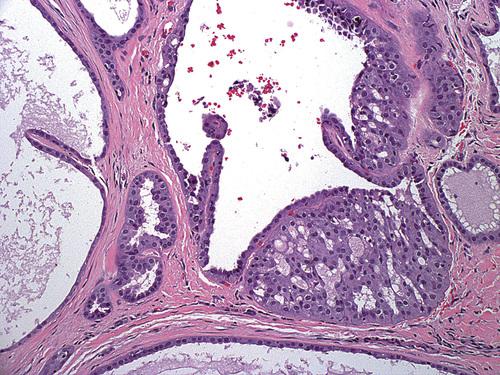

- Low-power photomicrograph showing a cyst below the mucosal surface.

- High-power view of cystic cavity lined by thin cuboidal epithelium. Adjacent to the cyst is an excretory salivary gland duct lined by columnar epithelium.

salivary duct cyst

This dilated duct is lined by columnar eosinophilic oncocytes that exhibit papillary folds into the ductal lumen. Such lesions may develop secondary to ductal obstruction.

salivary ductal ectasia